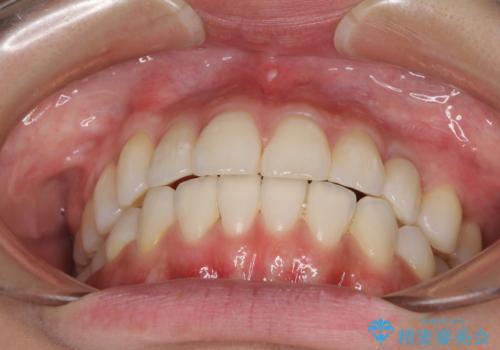

インプラント治療は当初の狙い通り、矯正治療期間中に行い、スムーズに処置を進めることができました。

歯並びが整ったことで治療前に認められた歯肉炎は全くなくなり、患者様には大変満足していただきました。